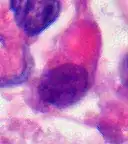

Examination of the cerebrospinal fluid is important (CSF), as one-third of patients will have intracranial dissemination with involvement of the CSF. Large tumor cells, eccentricity of the nuclei, and prominent nucleoli are consistent findings.[21] Usually only a minority of AT/RT biopsies have rhabdoid cells, making diagnosis more difficult. Increasingly it is recommended that a genetic analysis be performed on the brain tumor, especially to find if a deletion in the INI1/hSNF5 gene is involved (appears to account for over 80% of the cases). The correct diagnosis of the tumor is critical to any protocol. Studies have shown that 8% to over 50% of AT/RT tumors are diagnosed incorrectly.